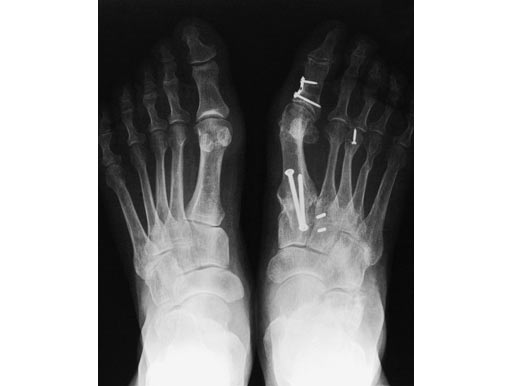

Case 1: 62-year-old female

One year after modified Lapidus operation with screws in the right foot. Now new treatment with an X-Plate (medium size) in the left foot.

Compared to screw osteosynthesis in the right foot, full weight bearing was possible after 6 weeks instead of 12 (see Fig 4)